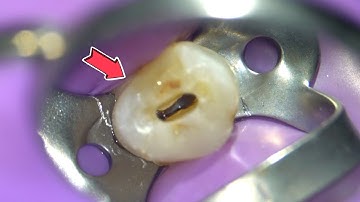

Root Canal Procedure Step by Step